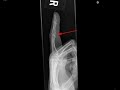

Volar plate avulsion fracture

This is a patient who presented with pain and swelling of the index finger following a hyperextension injury. Frontal and lateral radiographs were obtained. The frontal radiograph demonstrates circumferential soft tissue swelling of the finger, which is most prominent at the proximal interphalangeal joint. The lateral radiograph demonstrates a minimally displaced fracture from the volar base of the middle phalanx as indicated by the red arrow. This fracture represents an avulsion fracture where the volar plate pulls off a small piece of bone at its attachment site. The volar plate attaches the volar aspect of the proximal phalanx to the middle phalanx. With forceful hyperextension, the volar plate may either tear or my avulse a small piece of bone, as in this case.